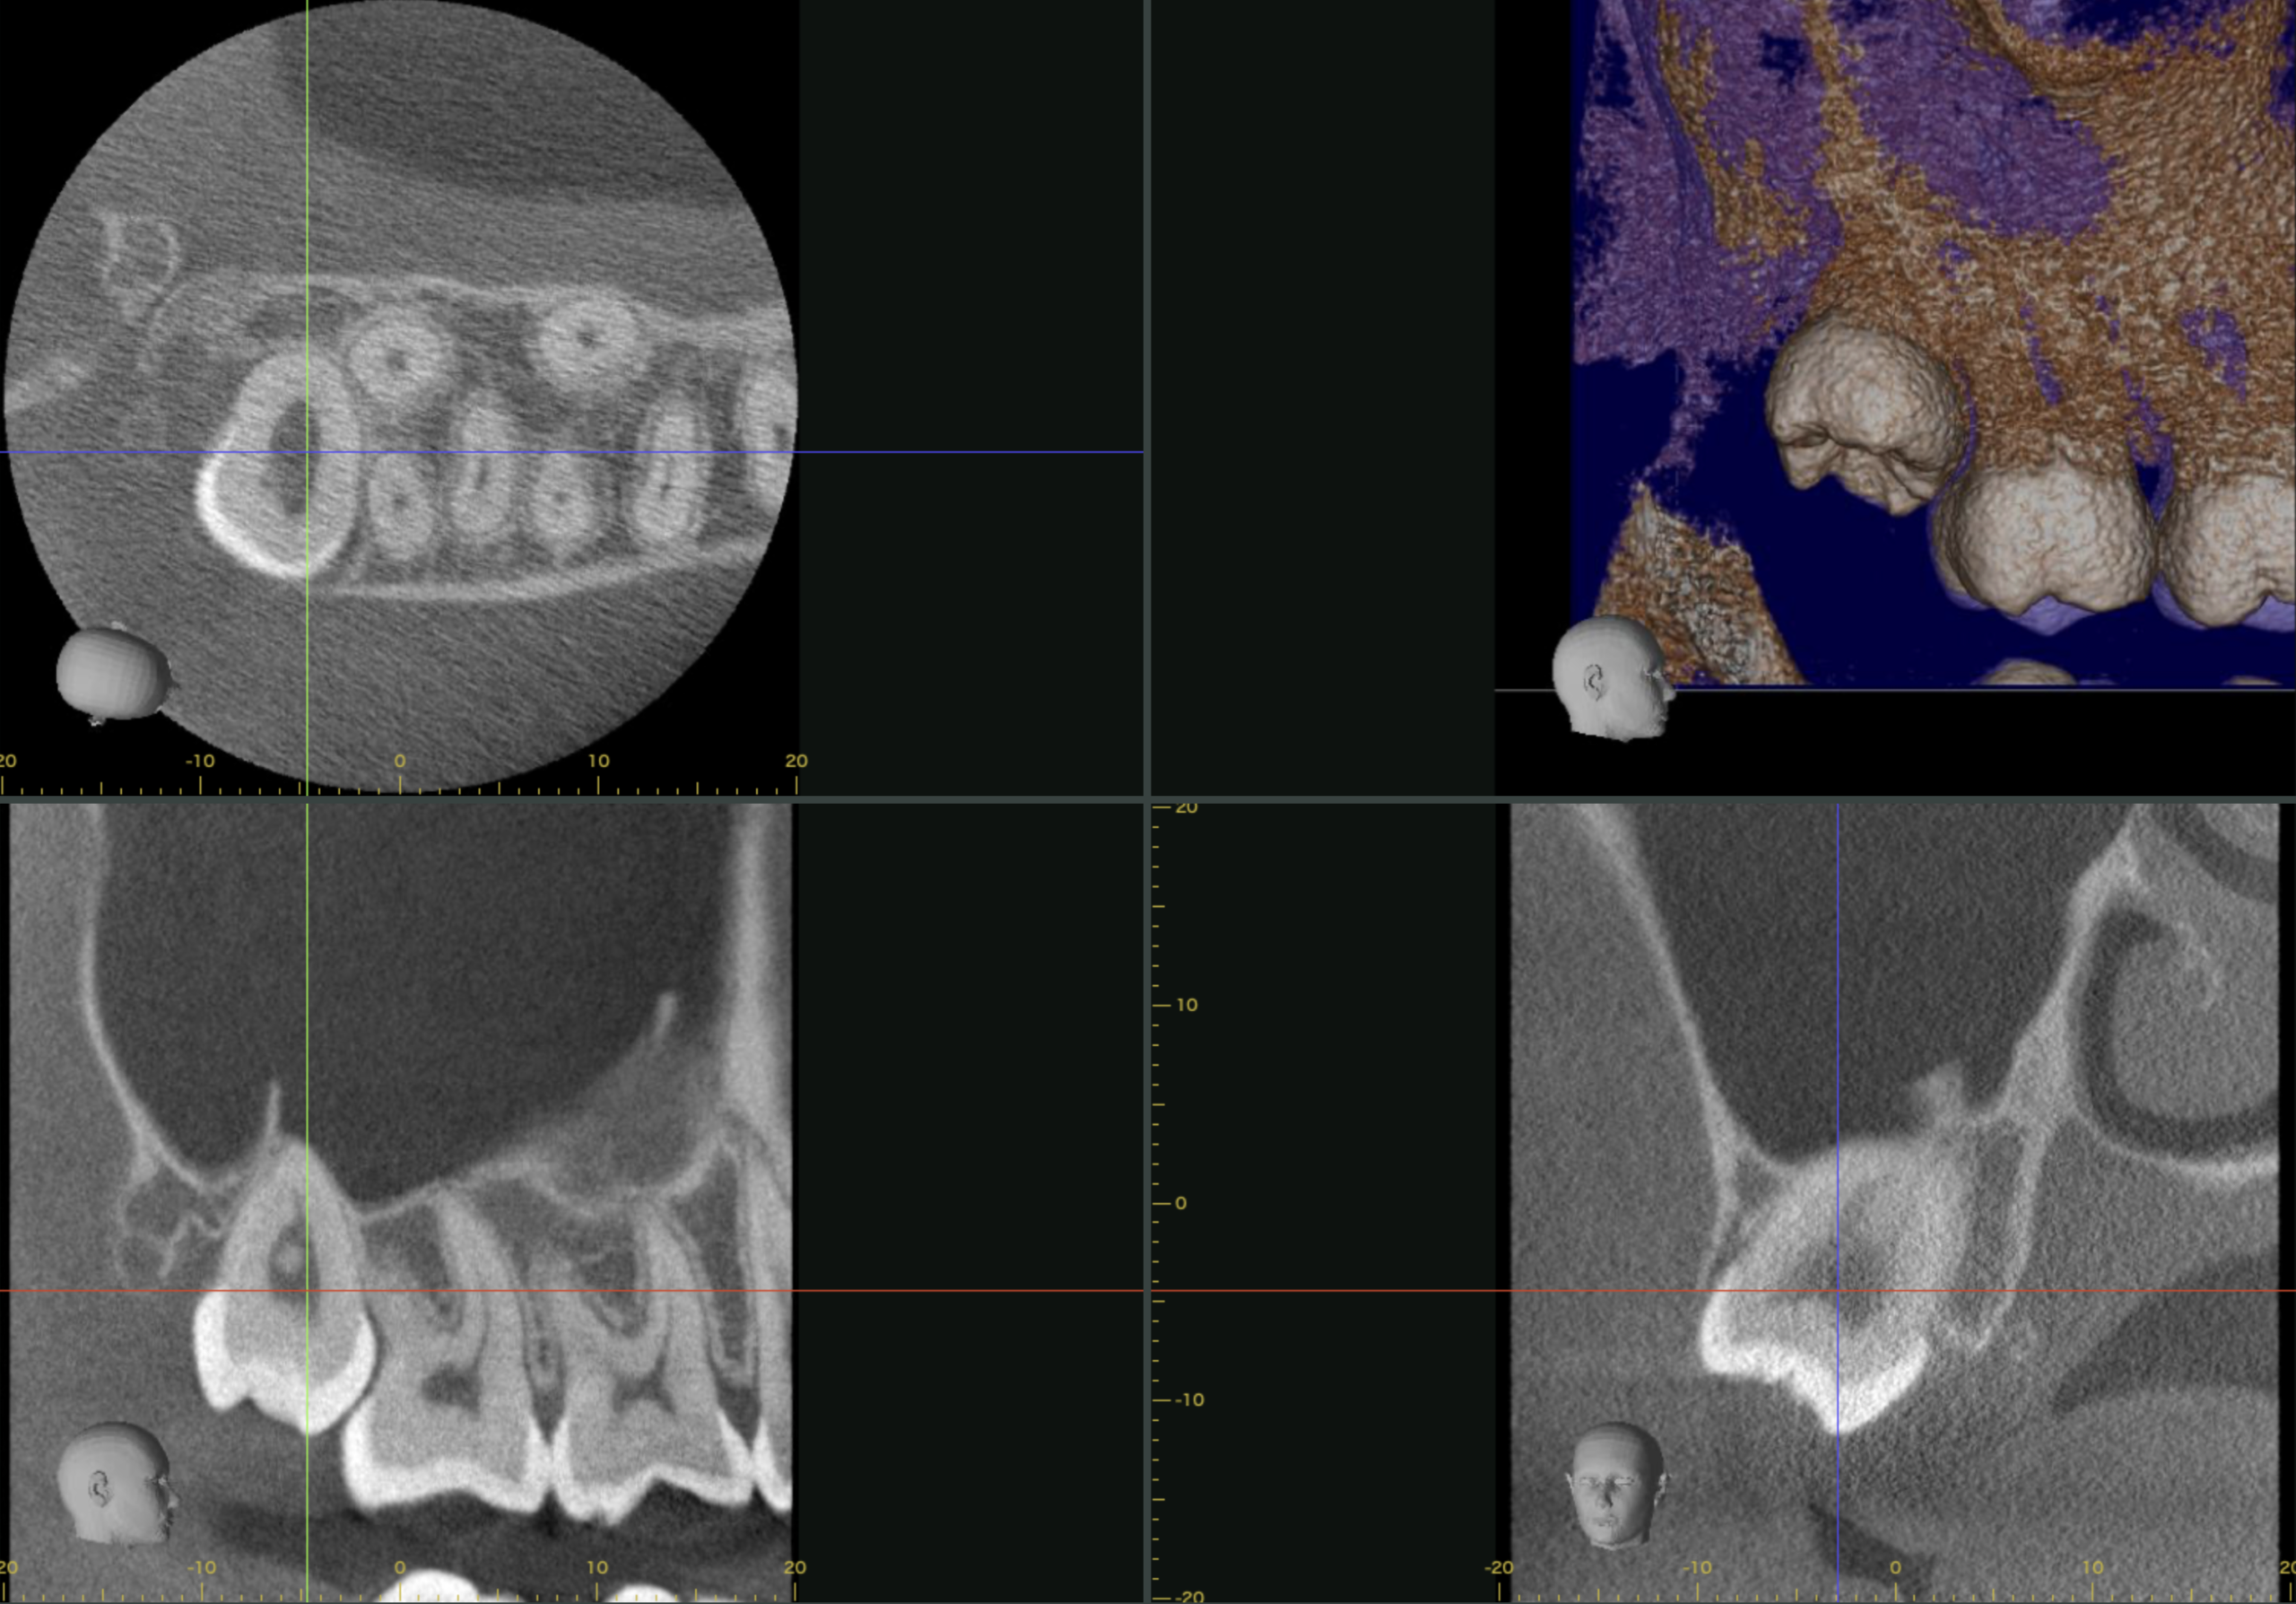

先ほどのパノラマ写真に比べ少し色がついたこちらは、

上記の画像はスクリーンショットなので動かせませんが、実際には画像を動かしながら立体的に見ていきます。